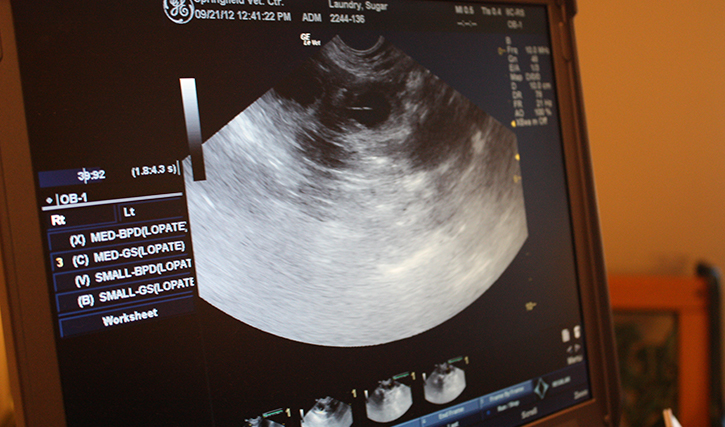

- Full pregnancy ultrasound

- Gestational aging via ultrasound